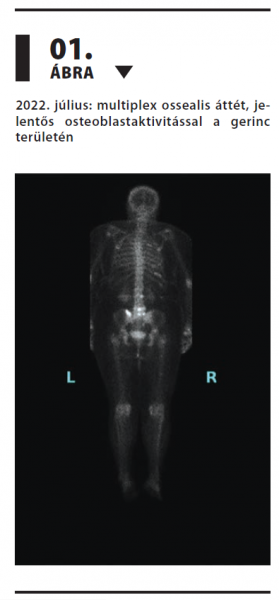

Tripla-negatív metasztatikus emlőrák hosszan tartó, sikeres kezelése szacituzumab-govitekánnal

Az emlőrák Magyarországon továbbra is a nők leggyakoribb daganatos betegsége. A Nemzeti Rákregiszter adatai szerint 2021-ben 7656 új esetet igazoltak,1 így a daganatos halálozás egyik vezető oka hazánkban is. Az áttétes tripla-negatív emlőrák prognózisa különösen rossz, a modern kezelések ellenére is. Esetünkben egy szokatlanul hosszú ideig szacituzumab-govitekán kezelésben részesülő nőbeteg történetét mutatjuk be, relatíve jó életminőség megtartása mellett.